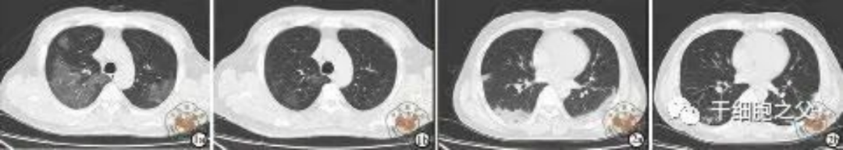

與安慰劑組相比,人臍帶間充質干細胞修復組全肺病變體積改善了10.8%,并且人臍帶間充質干細胞修復組在每一個隨訪節點都顯示出固體組分病變體積比例減少。此外,人臍帶間充質干細胞組有17.9%的患者在12個月時CT圖像變為正常,而安慰劑組沒有。

細胞輸注后,炎癥指標改善,復查胸部CT提示雙肺病灶較前吸收,呼吸道癥狀改善,新型冠狀病毒核酸檢測連續2次陰性,治愈出院。

研究結果:細胞輸注后,炎癥指標改善,復查胸部CT提示雙肺病灶較前吸收,呼吸道癥狀改善,新型冠狀病毒核酸檢測連續2次陰性,治愈出院。